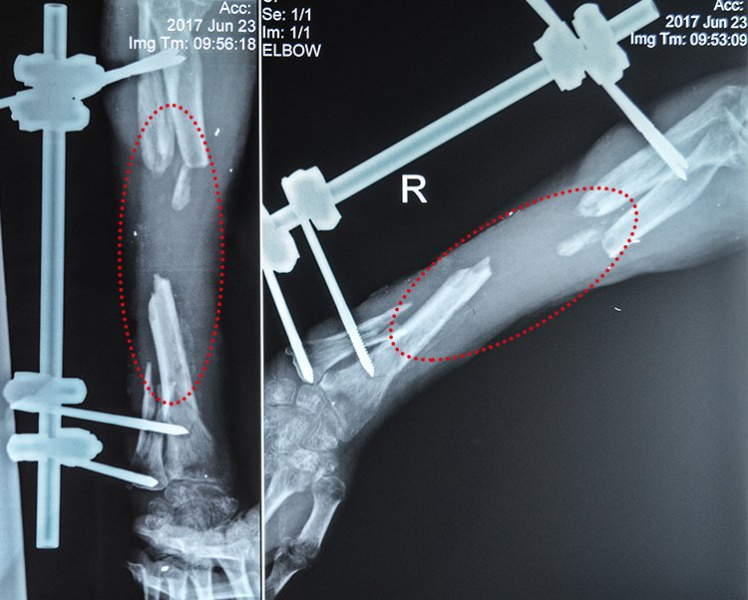

"Дефекти променевої та ліктьової кісток перевищують 10 см, крім того, триває вогнепальний остеомієліт, який продовжує руйнувати кісткову тканину. Зараз потрібно якнайшвидше зупинити цей небезпечний процес, після чого відновити кістки за допомогою біотехнологій", - повідомили на сайті.

Володимир має значні дефекти кісток передпліччя. За даними лікарів, їх практично неможливо якісно вилікувати за допомогою загальноприйнятих методик. Крім того, вогнепальний остеомієліт прогресує та невпинно погіршує ситуацію: збільшує дефект кісткової тканини і з часом може призвести до втрати руки.